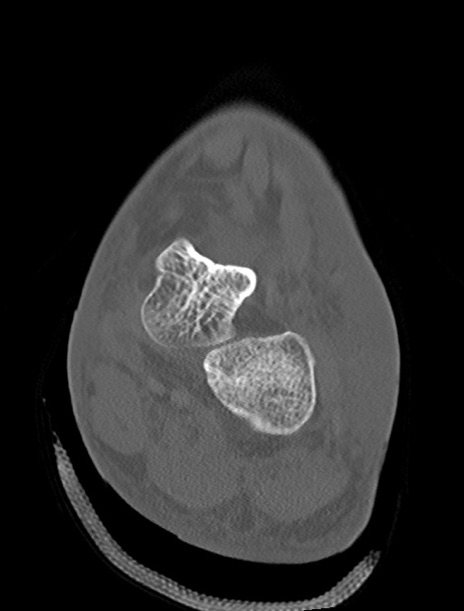

左足関節CT

横断像